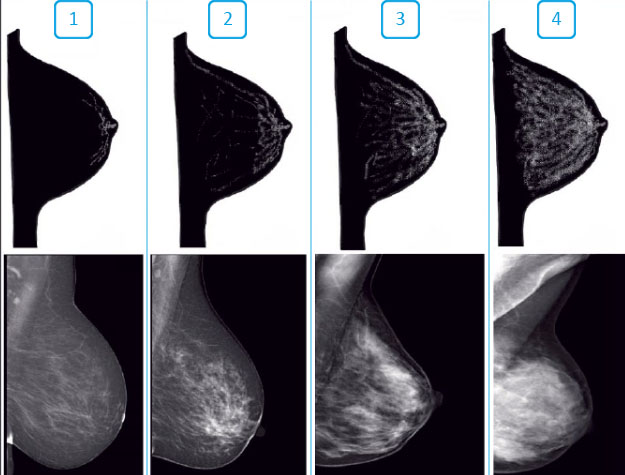

Различают четыре типа строения:

-

Жировой тип строения молочных желез встречается в 43% случаев и выглядит темным на снимке, на его фоне четко определяются любые изменения. Наиболее эффективный метод исследования – маммография.

Отдельные участки железистой ткани.

Умеренно выраженная железистая ткань.

Чрезвычайно выраженная железистая ткань.

Высокая маммографическая плотность у женщин после 40 лет встречается в 40–50 % случаев, является высоким и наследуемым показателем риска развития рака молочной железы. На плотном рентгеновском фоне на маммографии могут быть пропущены как доброкачественные, так и злокачественные образования. Поэтому со 2 и 3 типом старения УЗИ наиболее результативно.